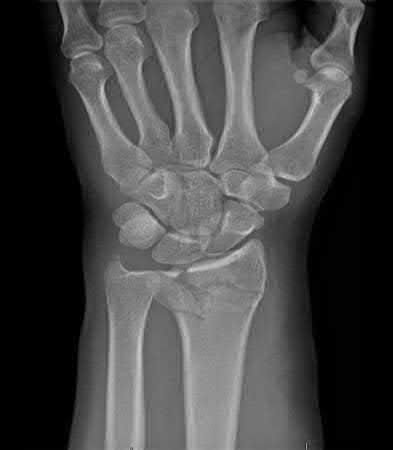

A 38-year-old male suffers the injury shown in Figure A. During operative fixation, free osteoarticular fragments are encountered and reconstruction of these pieces is attempted. Postoperatively, which of the following will have the most beneficial effect on the healing potential of the surviving chondrocytes within these reconstructed articular segments?

Figure A demonstrates a comminuted tibial plateau fracture with significant intra-articular involvement. Basic science evidence has demonstrated that post-operative gentle compressive loading may have a positive impact on articular cartilage healing; however, excessive shear loading may be detrimental.

Irrgang et al provide guidelines for rehabilitation following surgical management of articular cartilage lesions of the knee. They state that after articular cartilage repair, exercises to enhance muscle function must be done in a manner which minimizes shear loading of the joint surfaces in the area of the lesion. The authors also discuss the benefits of gentle compressive loading and motion of the joint, and its positive effects on chondrocyte nutrition.

Furthermore, they recommend a period of protected weight bearing as often being necessary, and that this should be followed by progressive loading of the joint.